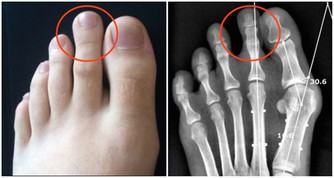

部分研究指出,定期捐血與降低某些癌症(如肝癌與肺癌)風險之間存在一定關聯,特別是體內鐵含量偏高者。